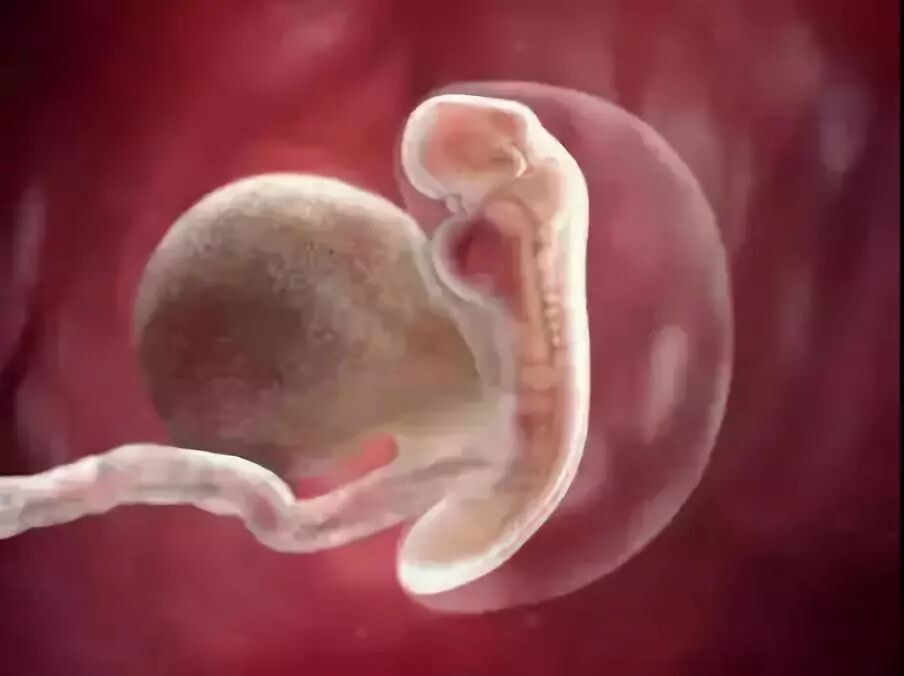

第5周

ta的小心脏开始有规律地跳动

第7周

ta长出了圆圆的手和脚

第10周

五官慢慢变得清晰

还顶着一个大大的额头~

第18周

长出了白色、柔软的绒毛

就像一个小老头

第26周

对妈妈的声音越来越敏感

第34周

ta变得越来越强壮

很快就能见到妈妈了

到了第40周

身体发育成熟

终于来到妈妈的身边